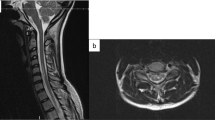

A case report of fibrocartilaginous embolism (FCE) presenting as acute myelopathy.

To illustrate the clinical presentation and magnetic resonance imaging features of FCE.

A 16-year-old boy was diagnosed with ischemic myelopathy secondary to FCE 2 years after symptom onset. Diagnosis was delayed because the clinical and radiological characteristics were not recognized initially. After rehabilitation, the patient made a modest recovery.

Diagnosis of FCE can be made by recognition of the characteristic clinical and radiological features and a high index of suspicion.